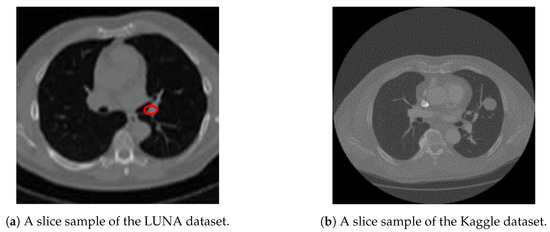

Once we trained the Deeplap-V3 plus [7] on the LUNA16 data, we run it on 2D slices of Kaggle dataset for nodule detection. However, as shown in Figure 9, Deeplab-V3 plus produces a strong signal for the actual nodule but also produces a lot of false positives, which would cause problems when training the classifier in the following stage of the pipeline.

Figure 9. Output nodule detection: Figure 9a shows the sample input from kaggle test set to the Deeplab model, and Figure 9b shows the Deeplab predicted output with a lot of false positives nodules.